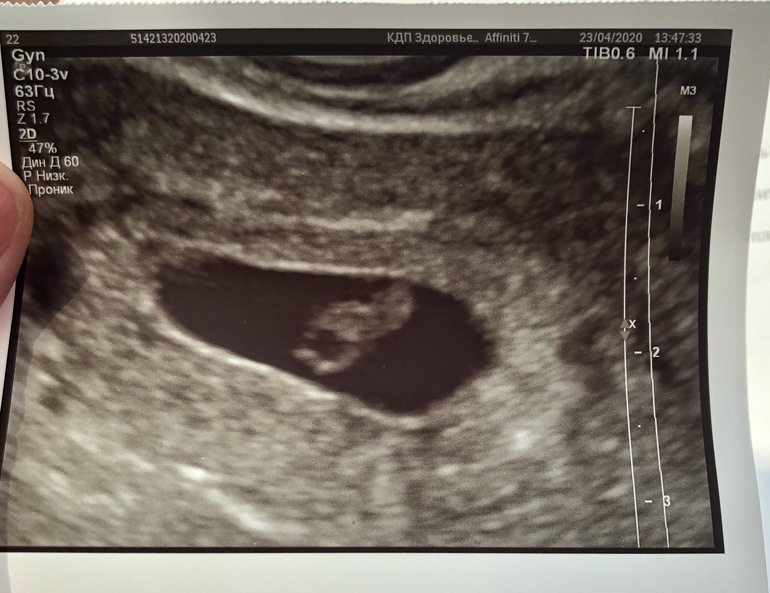

УЗИ 7.4 недель

Девочки, сходила сегодня на узи. Все хорошо. Размеры малыша соответствуют сроку. КТР 11,4 мм. ПЯ 23.5 мм. ЖМ 5 мм

СБ+, ЧСС 147 уд/мин.

Но поставили небольшой тонус(((

Даже ПЯ деформировано из-за этого. Немного переживаю..